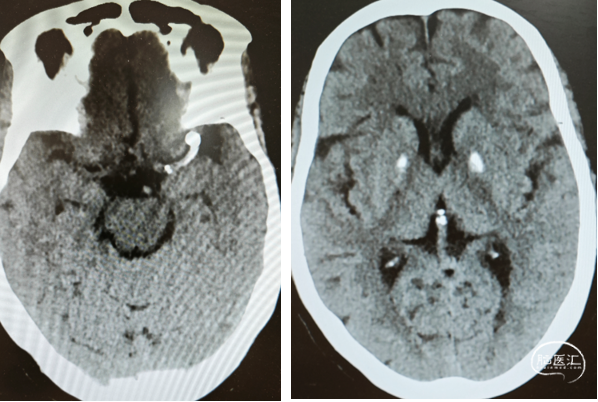

头颅CT

术前

术后第一天